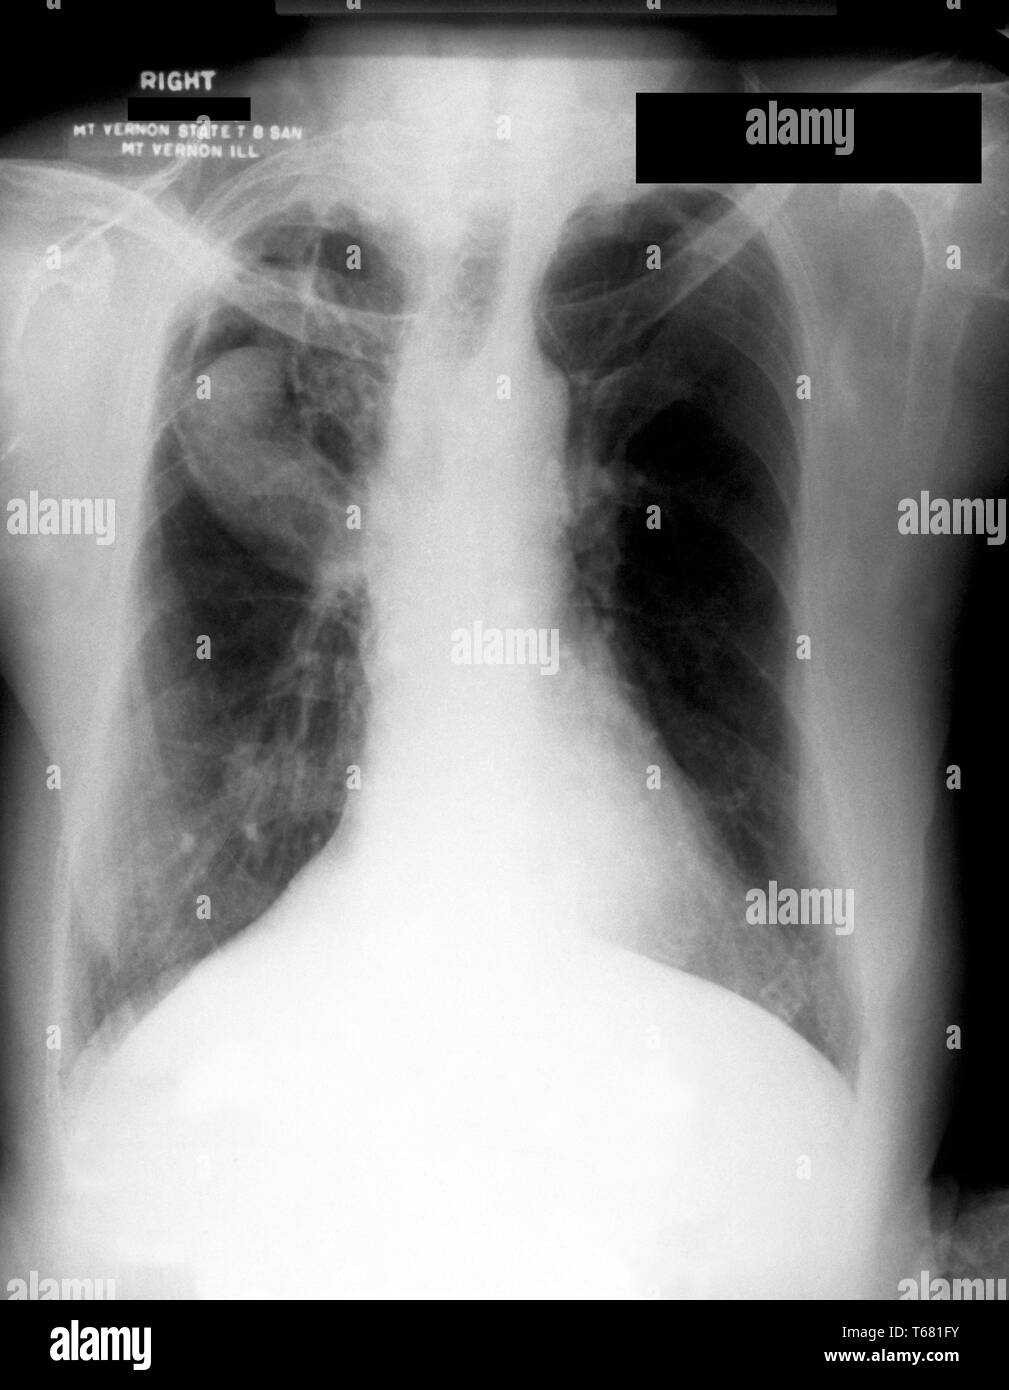

From www.researchgate.net

Chest Xray showed a fungus ball (yellow arrow), an air crescent with What Causes Fungus Balls Fungus balls in the sinus, also known as mycetomas, are typically caused by the overgrowth of fungi in the nasal cavity. Fungi build up in the sinuses and form a clump or ball. When people with lung cavities are also infected with aspergillus, fungus fibers may find their way into the cavities and grow into. Fungus balls, also known as. What Causes Fungus Balls.